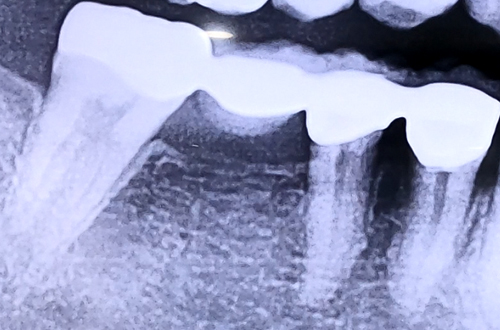

아주 오래전에 브릿지 치료를 받았던 어금니의 잇몸이 자꾸 붓고 염증이 생기고 씹을 때마다 통증이 있는 등의 증상으로 내원해주신 환자분입니다.

오른쪽 아래 뒤에서 두번째 큰 어금니를 예전에 발치한 뒤 브릿지 치료를 받으신 상태로, 브릿지 보철이 가진 단점 탓에 통증, 부기, 염증 등 잇몸 증상들이 나타나고 있는 상태셨는데요.

브릿지가 가진 특징 때문에 생기는 증상이므로, 브릿지를 제거한 뒤 치아 한 개씩 정상적인 힘만 받도록 개별적으로 치아를 씌워드리고 이가 없는 자리에는 임플란트를 식립하여 치료해 드렸습니다.